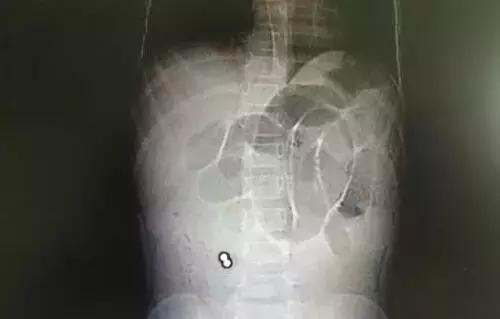

温温在惠州市第三人民医院门诊拍了胸片,提示:两个高密度影,伴有肠梗阻表现。如片子所示,患者右下腹可见两个圆圆的小球,颜色越白,说明物体的密度越高,高度怀疑是小铁球之类的东西。

这个东西到底是什么呢?后来温温做了个CT,高度提示是消化道异物、肠梗阻及包裹。医生反复询问小姑娘及其父母,他们都否认吞服过异物。这两个小球紧紧地挨在一起,莫非……果然,温温的妈妈承认家中确实有巴克球(磁力球)。

因为病情严重,温温被紧急送往手术室,术中发现她的部分肠管己经坏死。医生为她施行部分肠管切除及修补手术,并顺利取出了这两个小磁球-巴克球。